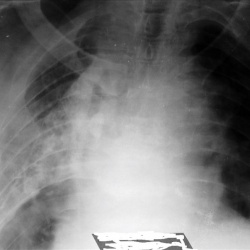

Травма.Женщина весьма преклонного возраста. 2 недели тому упала, "очень сильно болели ребра", но в поликлинику не пошла. Сейчас, со слов пациентки, болит все в груди.Направлена, в связи с травмой, на...